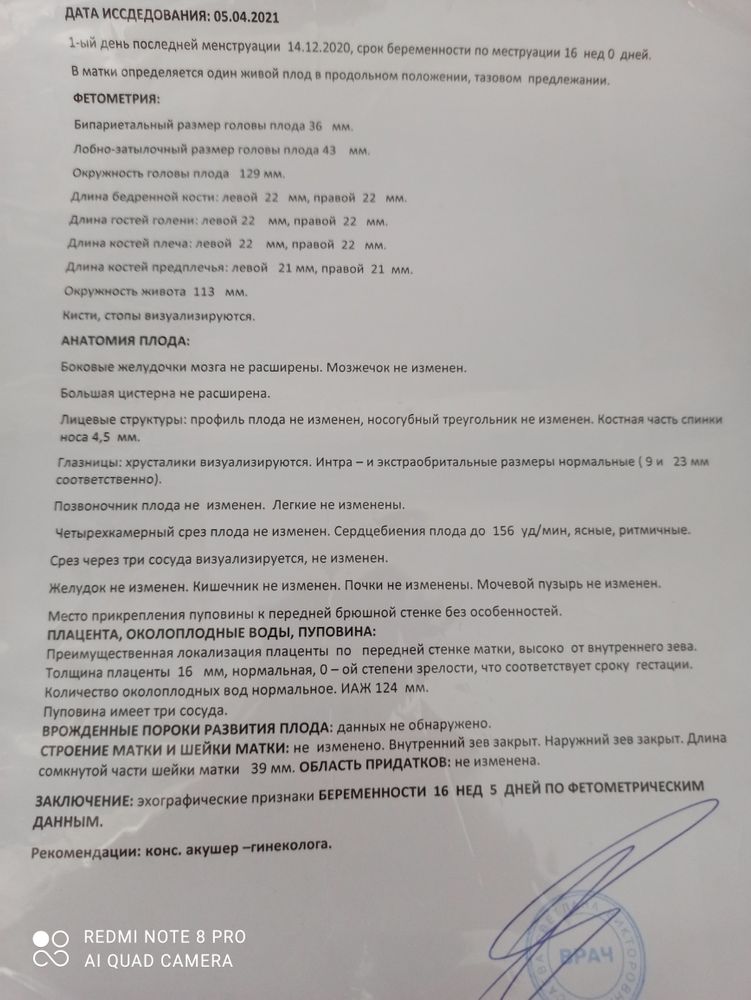

УЗИ, КТГ, доплер